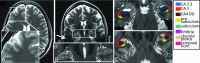

At ultra-high magnetic fields, such as 7T, MR imaging can noninvasively visualize the brain in unprecedented detail and through enhanced contrast mechanisms. The increased SNR and enhanced contrast available at 7T enable higher resolution anatomic and vascular imaging. Greater spectral separation improves detection and characterization of metabolites in spectroscopic imaging. Enhanced blood oxygen level-dependent contrast affords higher resolution functional MR imaging. Ultra-high-field MR imaging also facilitates imaging of nonproton nuclei such as sodium and phosphorus. These improved imaging methods may be applied to detect subtle anatomic, functional, and metabolic abnormalities associated with a wide range of neurologic disorders, including epilepsy, brain tumors, multiple sclerosis, Alzheimer disease, and psychiatric conditions. At 7T, however, physical and hardware limitations cause conventional MR imaging pulse sequences to generate artifacts, requiring specialized pulse sequences and new hardware solutions to maximize the high-field gain in signal and contrast. Practical considerations for ultra-high-field MR imaging include cost, siting, and patient experience.